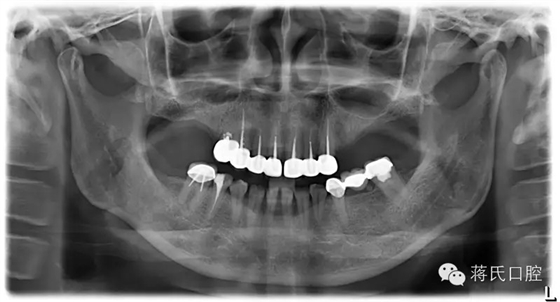

患者情況女 49歲,三類骨,右上區(qū)骨高度6毫米,寬度8毫米。左上區(qū)骨最低點1毫米,寬度3毫米

種植前X線,左側(cè)外提升右側(cè)內(nèi)提升